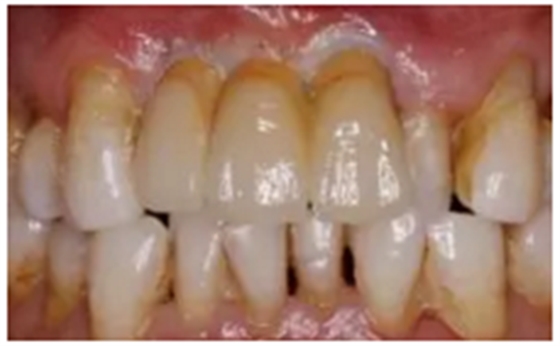

(5)個(gè)性化基臺(tái)及臨時(shí)修復(fù)體戴入,軟組織成形

7.png